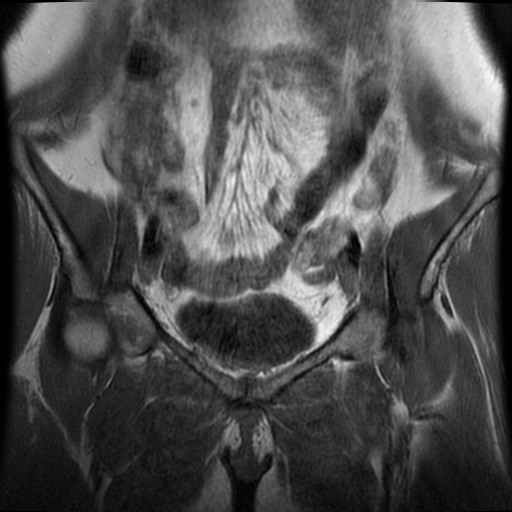

Bekken